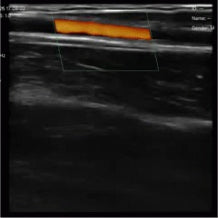

Real life images

Our devices reproduce excellent image quality.